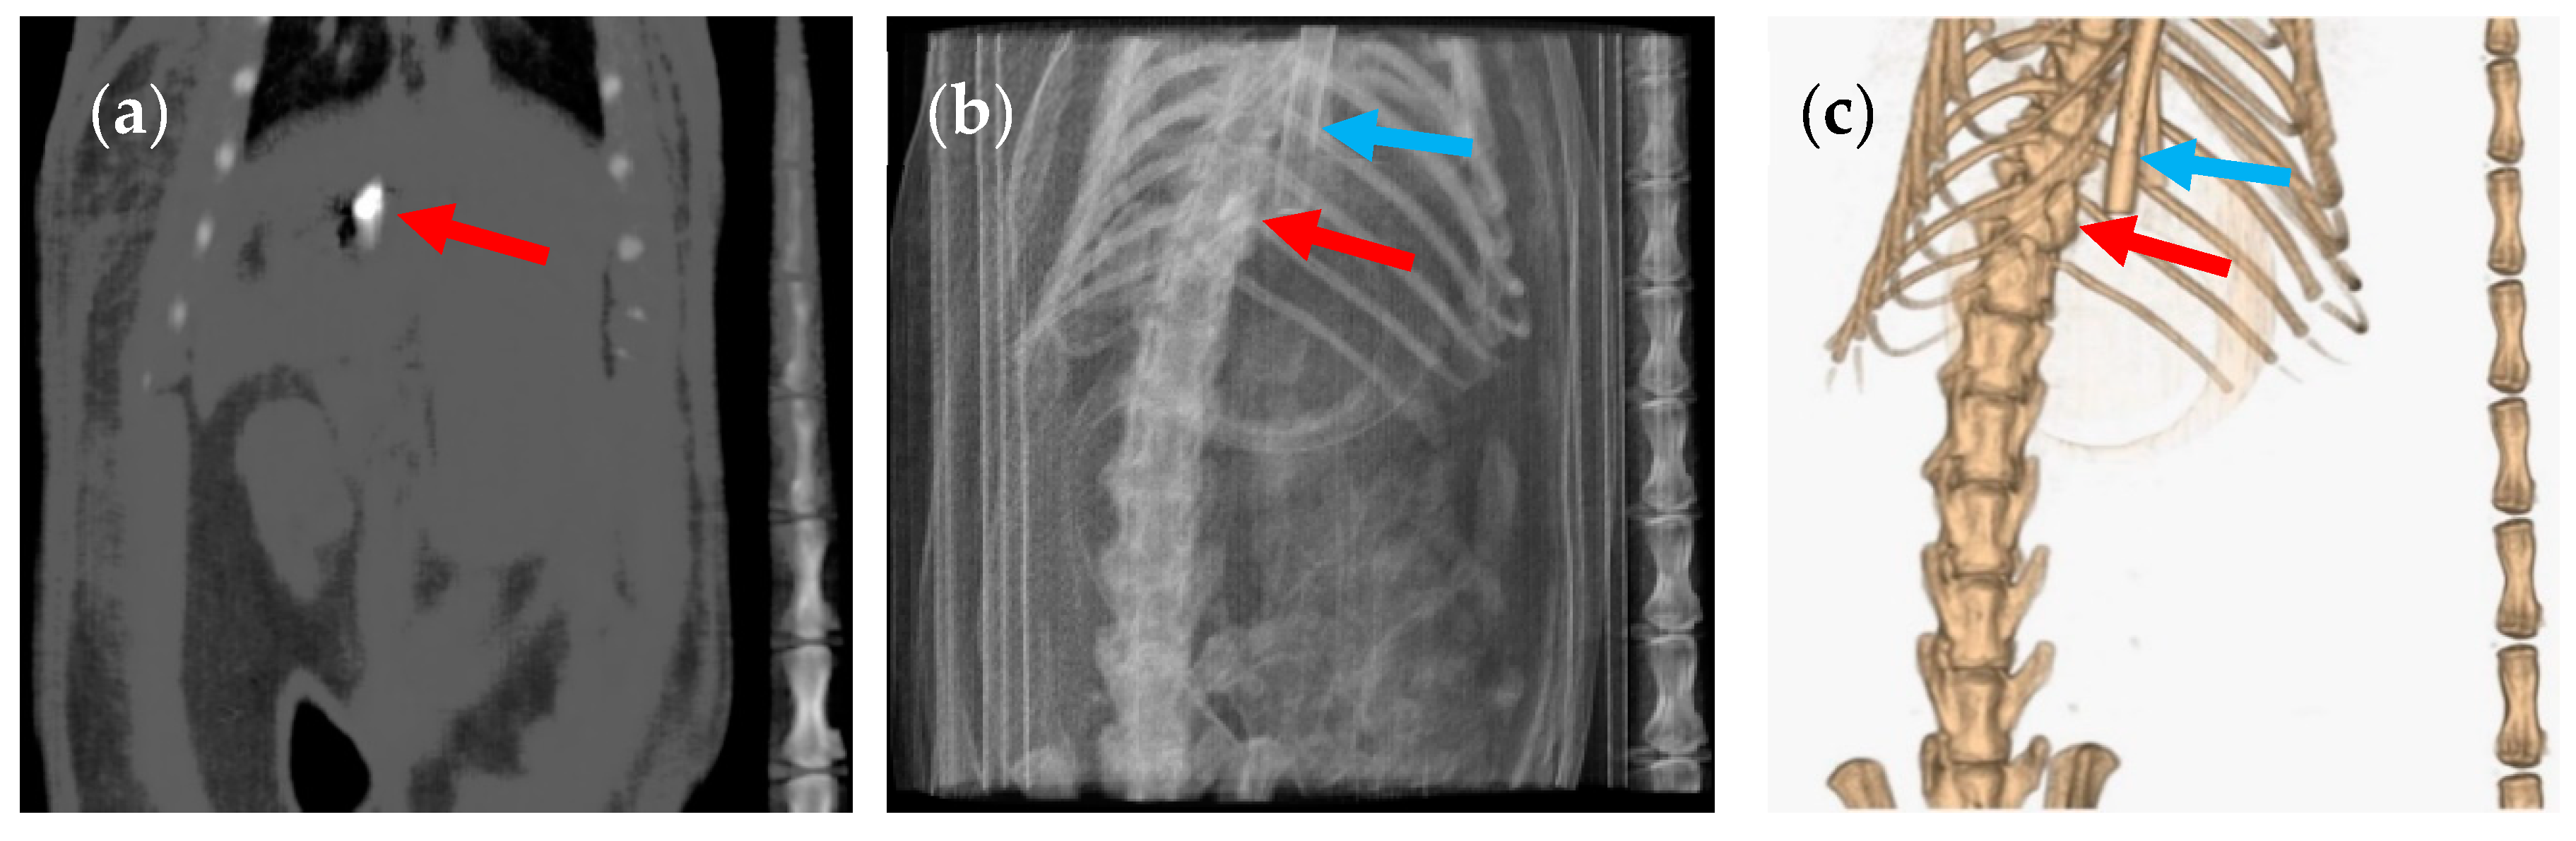

3. Results and Discussion